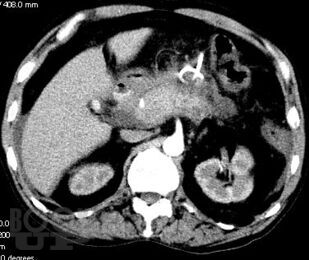

Учебно-методическое пособие посвящено актуальным проблемам этиологии, патогенеза, диагностики, современным методам консервативного и оперативного лечения острого панкреатита Представлены новые классификации, схемы консервативного лечения, современные виды оперативного лечения. Иллюстрировано рисунками, таблицами, имеются тестовые задания и задачи. Пособие предназначено для ординаторов и слушателей дополнительного профессионального образования, обучающихся по специальности 31.08.67 Хирургия.